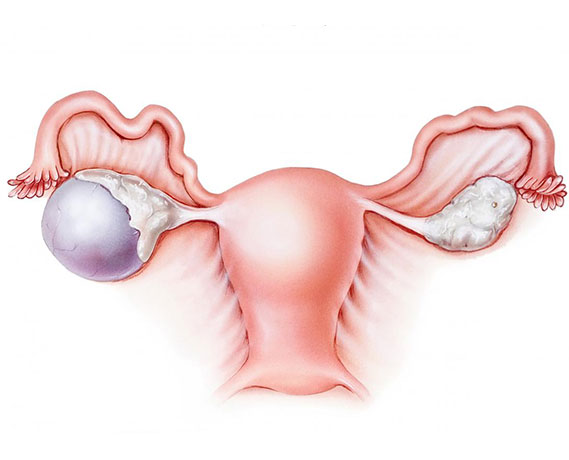

Myomların klinik bulguları genellikle lokalizasyonları ile ilişkilidir. Rahim kavitesinin içine doğru büyüyen submüköz myomlar, uzamış ve ağır kanamaya neden olurlar. Bu myomlar aynı zamanda gebe kalmak isteyen kadınlarda da problem yaratırlar. Subseröz myomlar ise rahimin dış kısmına doğru büyüyen myomlardır. Bazen mesaneye bası yaparak idrar ile ilgili şikayetlere neden olabilirler. Eğer rahmin arka tarafına doğru büyürlerse rektuma bası ile kabızlık, spinal sinirlere bası ile bel ağrısına neden olabilirler.

Myomlar, genellikle gebe kalmaya engel olmasalar bile yerleşim yerlerine bağlı olarak spermlerin rahim içine girişlerine ya da tüplerden geçişine engel olabilirler. Yine rahim iç tabakasına yerleşmiş olan myomlar embriyo gelişimini engelleyebilirler. Gebelikte ise myomlar sıklıkla karın ve kasık ağrısı şikayetine neden olurlar. Bazı nadir durumlarda ise düşük ya da erken doğuma sebebiyet verebilirler.